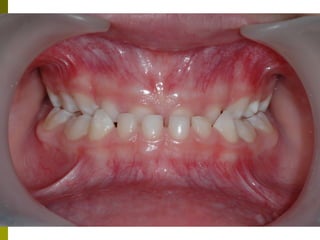

Μόνιμη οδοντοφυΐα 10 + ετών

 Παρακολουθούμε την ολοκλήρωση

αλλαγής δοντιών

 Ελέγχονται ορθοδοντικές ανωμαλίες

 Θεραπευτική αντιμετώπιση μονίμων

δοντιών

 Καλό προληπτικό πρόγραμμα,

εξατομηκευμένο

Μόνιμη οδοντοφυΐα 10+ ετών  Παρακολουθούμε την ολοκλήρωση αλλαγής δοντιών  Ελέγχονται ορθοδοντικές ανωμαλίες  Θεραπευτική αντιμετώπιση μονίμων δοντιών  Καλό προληπτικό πρόγραμμα, εξατομηκευμένο